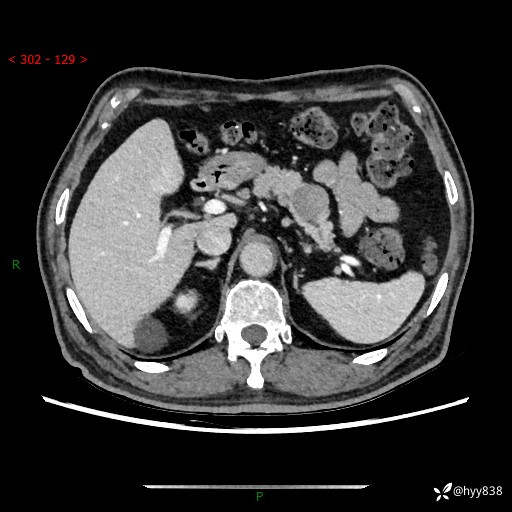

69岁/男,四肢无力3月余。胰腺囊实性占位,渐进性强化---结果公布~

【患者信息】:69岁/男

【主诉】:四肢无力3月余。

【现病史及既往史】:患者3月前无明显诱因出现四肢乏力,伴有口干、多饮、多尿等症状,无畏寒、发热、恶心、腹痛、腹泻等其他症状,于2024-06-13来我院住院治疗,完善相关辅助检查后,考虑“2型糖尿病”,予以降糖(阿卡波糖片 50mg po tid、德谷门冬双胰岛素注射液 8iu 早餐前 皮下注射)等治疗,口干、多饮、多尿较前缓解,血糖控制可;现仍存在四肢乏力,于2024-08-28来我院门诊就诊,查血钾2.88 mmol/L ,现以“低钾血症”收入我科。 本次起病以来,患者精神、饮食、睡眠良好,二便正常,近3月余体重下降约5kg。

【检查】:胰腺CT平扫+增强